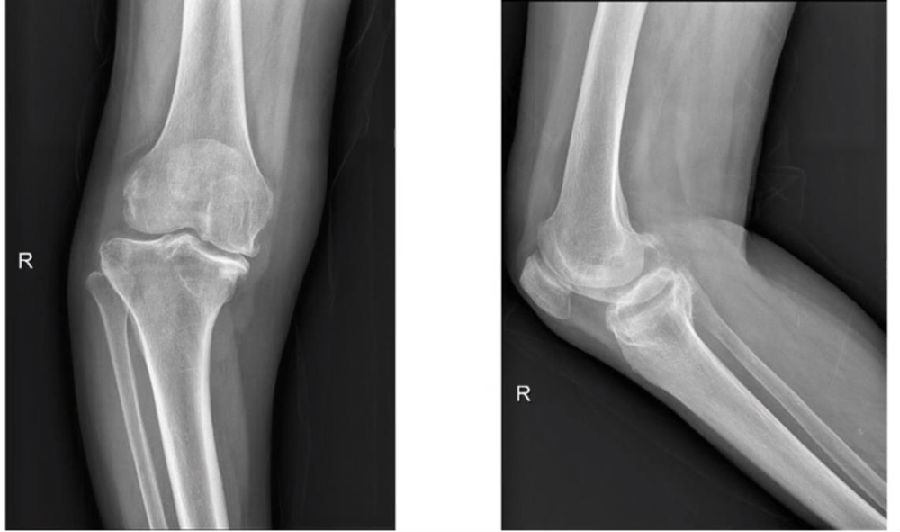

图8 术前影像(R)

图9 完成导航注册后获得患者畸形角度(R)

图10 胫骨平台规划、截骨(R)

图11间隙测量(R)

图12 股骨远端规划(R)

图13 参照规划精确截骨(R)

图14 下肢力线(R)